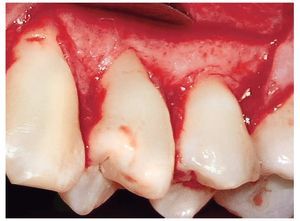

En ambos casos se empleó la técnica de colgajo de desplazamiento lateral pediculado unilateral para asegurar el cierre primario con la encía atravesando el ángulo línea distal del incisivo lateral. Antes de la cirugía, se suavizó la convexidad prominente de la raíz mediante fresas de diamante. Se realizó una incisión en forma de V alrededor de la raíz denudada para eliminar el epitelio y tejido conectivo adyacentes. En la zona opuesta al área donante se biseló la incisión en V para permitir el solapamiento y aumentar la vascularidad del tejido donante en la zona (fig. 3). Las incisiones intrasulculares se extendieron distalmente a la recesión, a dos dientes. Se realizó una incisión de descarga hacia la mucosa, en correspondencia con el ángulo línea del segundo premolar (fig. 4).

Figura 3. Biselado de la incisión en forma de V.

Figura 4. Incisión vertical de descarga hacia la mucosa.